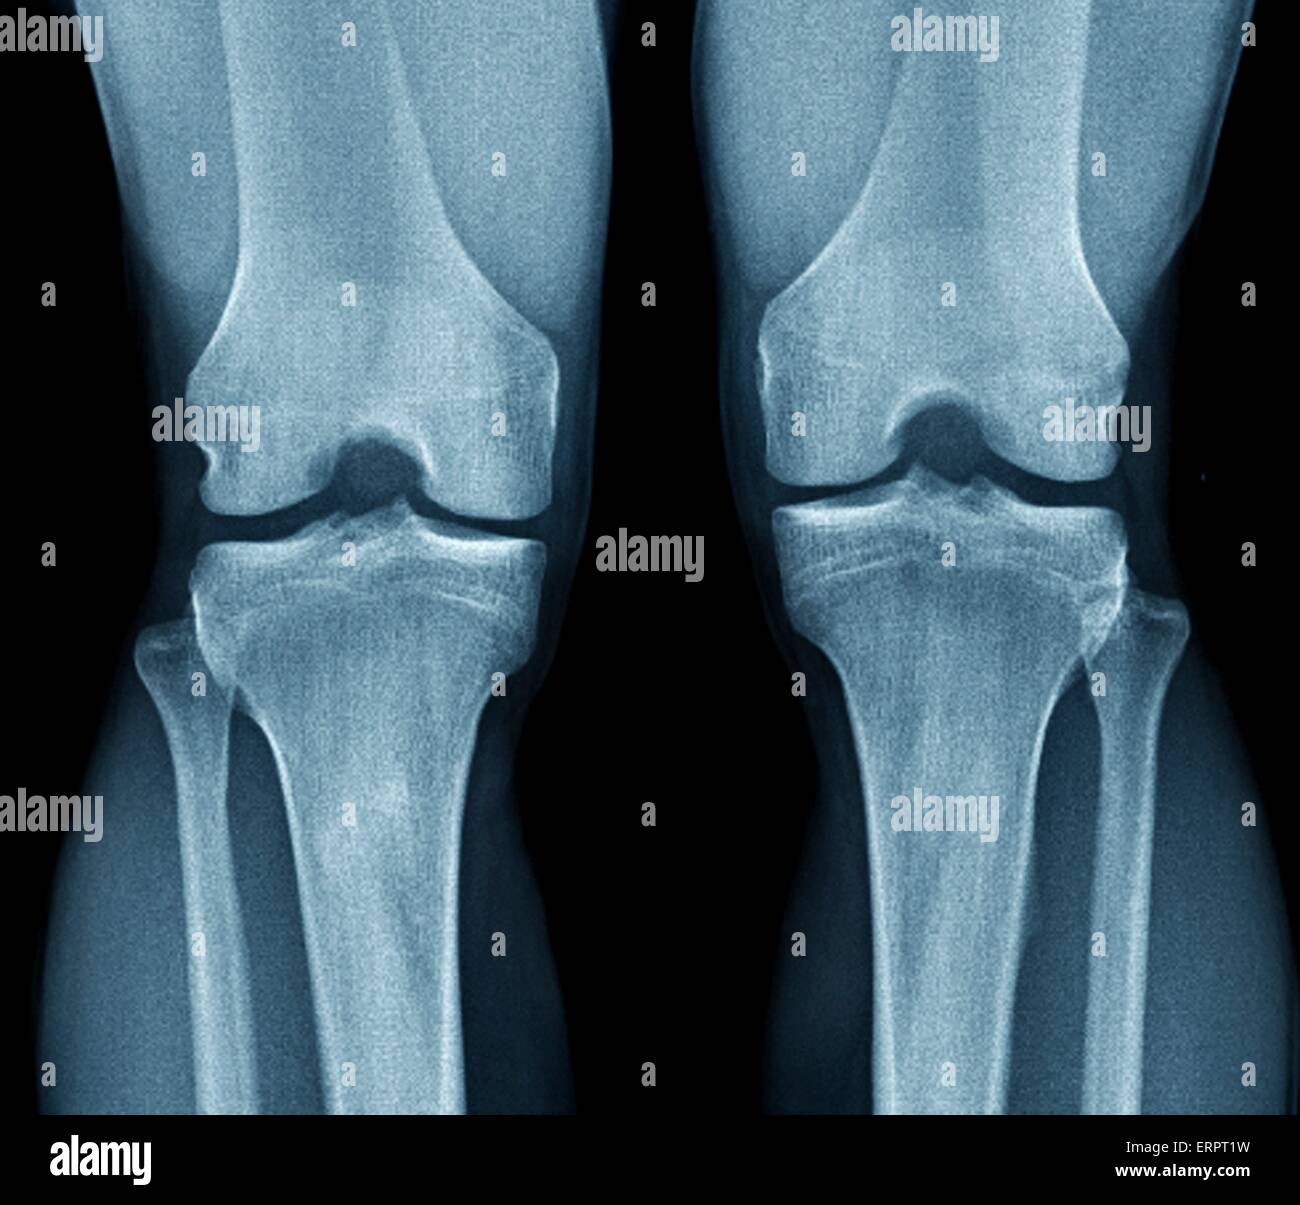

Film Xray Both Knee Joint AP View Name is Rosenberg View for Diagnosis Best View For Knee X Ray The horizontal beam lateral view allows identification of a knee joint effusion or lipohaemarthrosis (fat and blood in the joint) tibial plateau fractures can be very subtle and lipohaemarthrosis may be the only visible sign. the most common and standard for knee radiographs is the ap view or anteroposterior view. the rosenberg view of the knees is a. Best View For Knee X Ray.